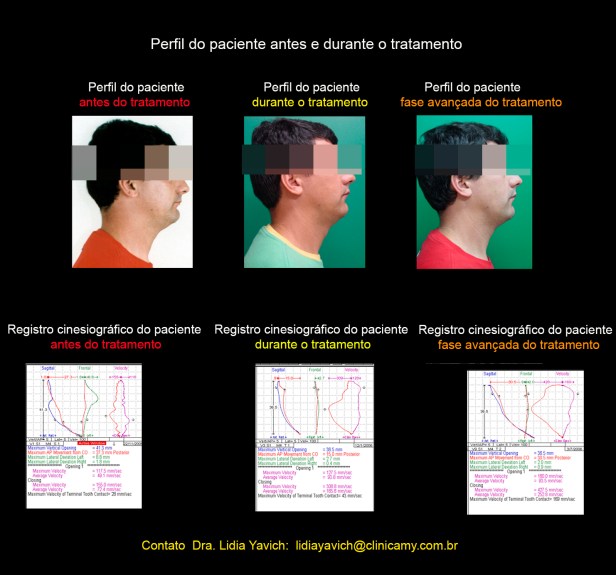

Esta imagem mostra uma sequencia do perfil do paciente conjuntamente com a sequência de registros cinesiográficos.

Estes registros tem que ser relacionados com os registros eletromiográficos postados anteriormente.

Todo fica correlacionado, descompressão articular, funcionamento dos músculos mastigatórios e a localização tridimensional da mandíbula.

O DIO (dispositivo intraoral) é planejado não só pela desprogramação eletrônica, mas também pelas imagens e outros auxiliares do diagnóstico. É controlado, trocado e recalibrado como parte de um tratamento.

O DIO deve ser mensurado eletromigráficamente. Logicamente a melhoria da sintomatologia do paciente deve acompanhar a melhoria dos registros.

Esta imagem mostra uma sequencia do perfil do paciente conjuntamente com a sequência de registros cinesiográficos e registros eletromiográficos.

Estes registros tem que ser relacionados com os registros eletromiográficos postados anteriormente.

Todo fica correlacionado, descompressão articular, funcionamento dos músculos mastigatórios e a localização tridimensional da mandíbula.

O DIO (dispositivo intraoral) é planejado não só pela desprogramação eletrônica, mas também pelas imagens e outros auxiliares do diagnóstico. É controlado, trocado e recalibrado como parte de um tratamento.

O DIO deve ser mensurado eletromigráficamente. Logicamente a melhoria da sintomatologia do paciente deve acompanhar a melhoria dos registros.

Perfil comparativo do paciente em oclusão habitual e em oclusão neuromuscular fisiológica com o Dispositivo Intraoral instalado. Melhora no posicionamento da cabeça.